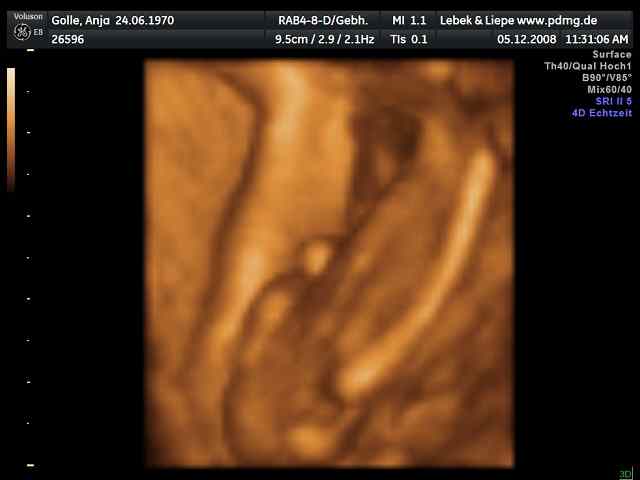

03/2006 => 1. IVM (D), POSITIV